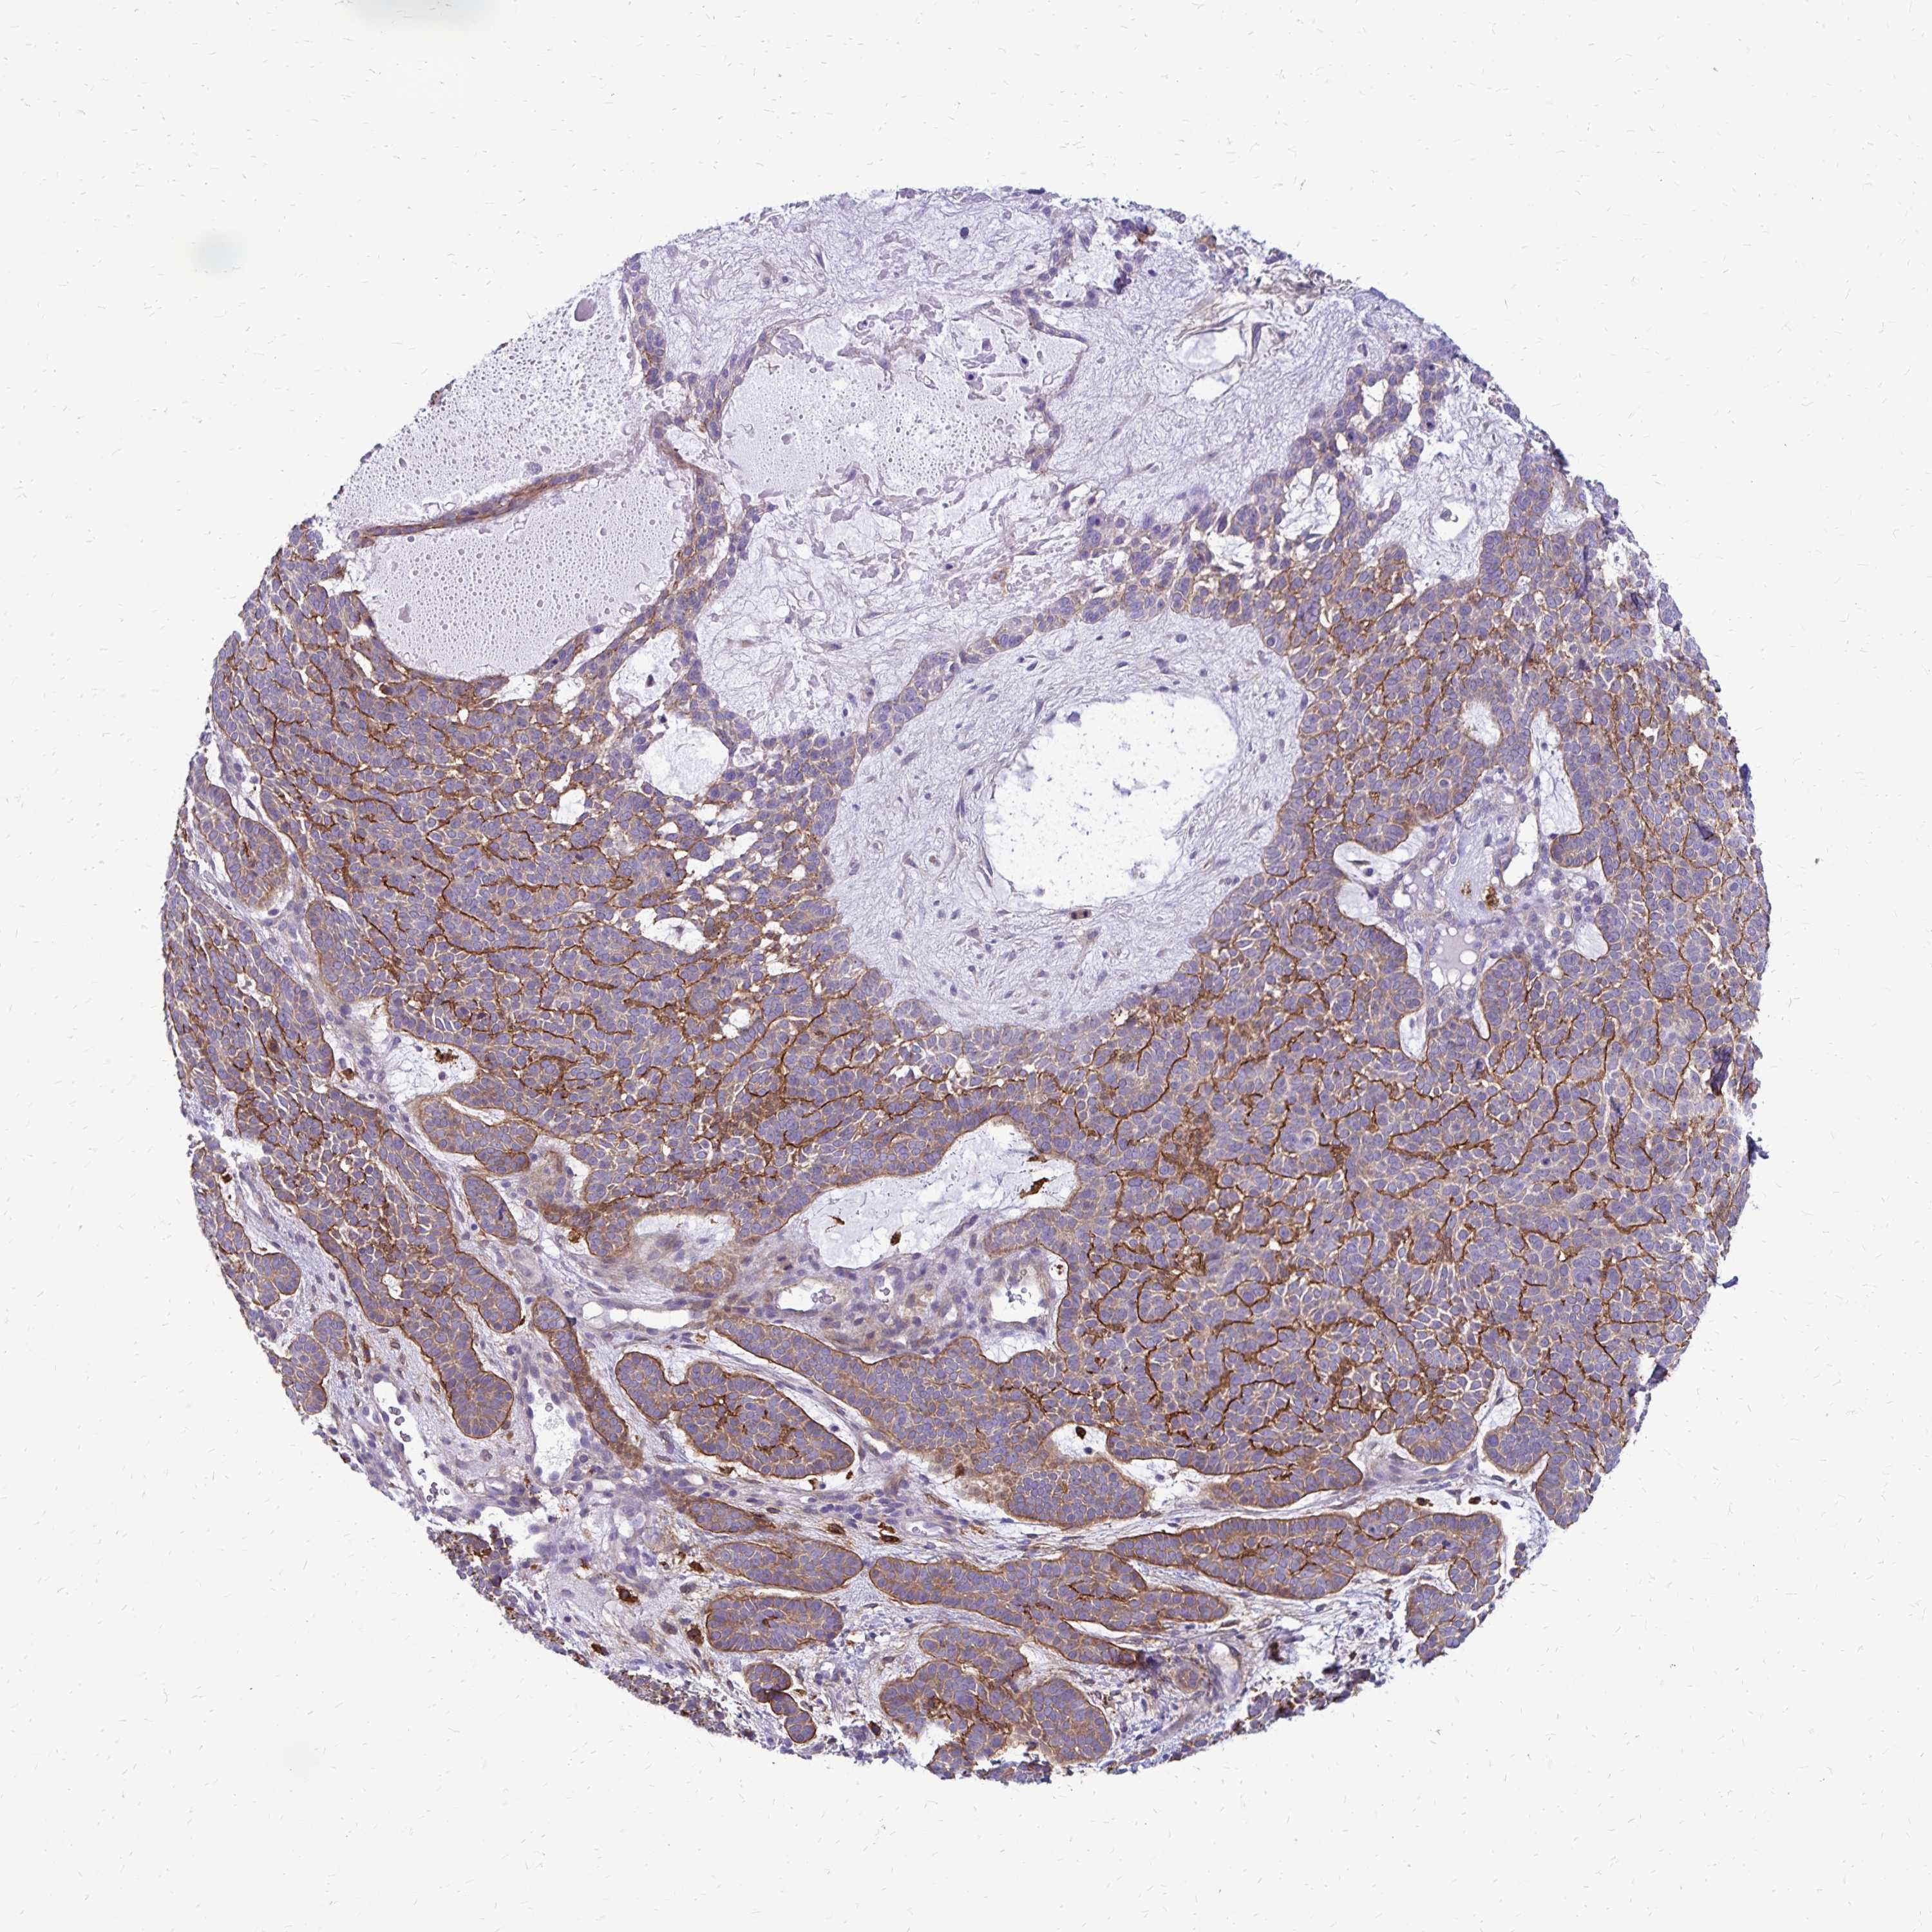

Basal cell and squamous cell cancer

SKIN CANCER - Protein expressioni

A mouse-over function shows sample information and annotation data. Click on an image to view it in a full screen mode. Samples can be filtered based on level of antibody staining by selecting one or several of the following categories: high, medium, low and not detected. The assay and annotation is described here.

Antibody stainingi

Antibody staining in the annotated cell types in the current human tissue is reported as not detected, low, medium, or high, based on conventional immunohistochemistry profiling in selected tissues. This score is based on the combination of the staining intensity and fraction of stained cells.

Each image is clickable and will lead to virtual microscopy that enables deeper exploration of all samples and also displays staining intensity scores, fraction scores and subcellular localization as well as patient and tissue information for each sample.

Antibody HPA055338

Antibody HPA056015

Staining

High

Medium

Low

Not detected

Intensity

Strong

Moderate

Weak

Negative

Quantity

>75%

75%-25%

<25%

None

Location

Nuclear

Cytoplasmic/membranous

Cytoplasmic/membranous,nuclear

Basal cell carcinoma

Squamous cell carcinoma, NOS